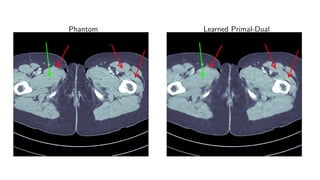

Results for ray transform inversion in 2D.

Compare to:

FBP

Total Variation

Post-processing deep learning by U-Net

Phantom Learned Primal-Dual

Method PSNR (dB) SSIM Runtime (ms) Parameters

FBP 33.65 0.829 423 1

TV 37.48 0.946 64 371 1

Learned U-Net 41.92 0.941 463 107

Learned Primal-Dual 44.11 0.969 620 2.4 · 105